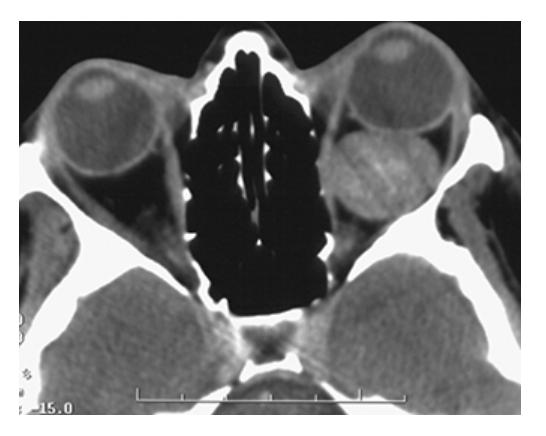

What does the figure show?

Cavernous Hemangioma. Noncontrast CT showing smoothly marginated, high-density, round, contrast-enhancing intraconal mass of the left orbit displacing the left globe anteriorly.